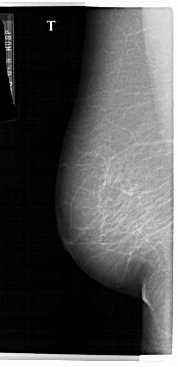

A_1579_1.LEFT_CC

A_1579_1.RIGHT_CC

LEFT_CC LINES 4531 PIXELS_PER_LINE 2041 BITS_PER_PIXEL 12 RESOLUTION 43.5 NON_OVERLAY

FILE: A_1579_1.RIGHT_CC.OVERLAY

TOTAL_ABNORMALITIES 1

ABNORMALITY 1

LESION_TYPE MASS SHAPE IRREGULAR MARGINS ILL_DEFINED

ASSESSMENT 4

SUBTLETY 1

PATHOLOGY MALIGNANT

TOTAL_OUTLINES 1

BOUNDARY